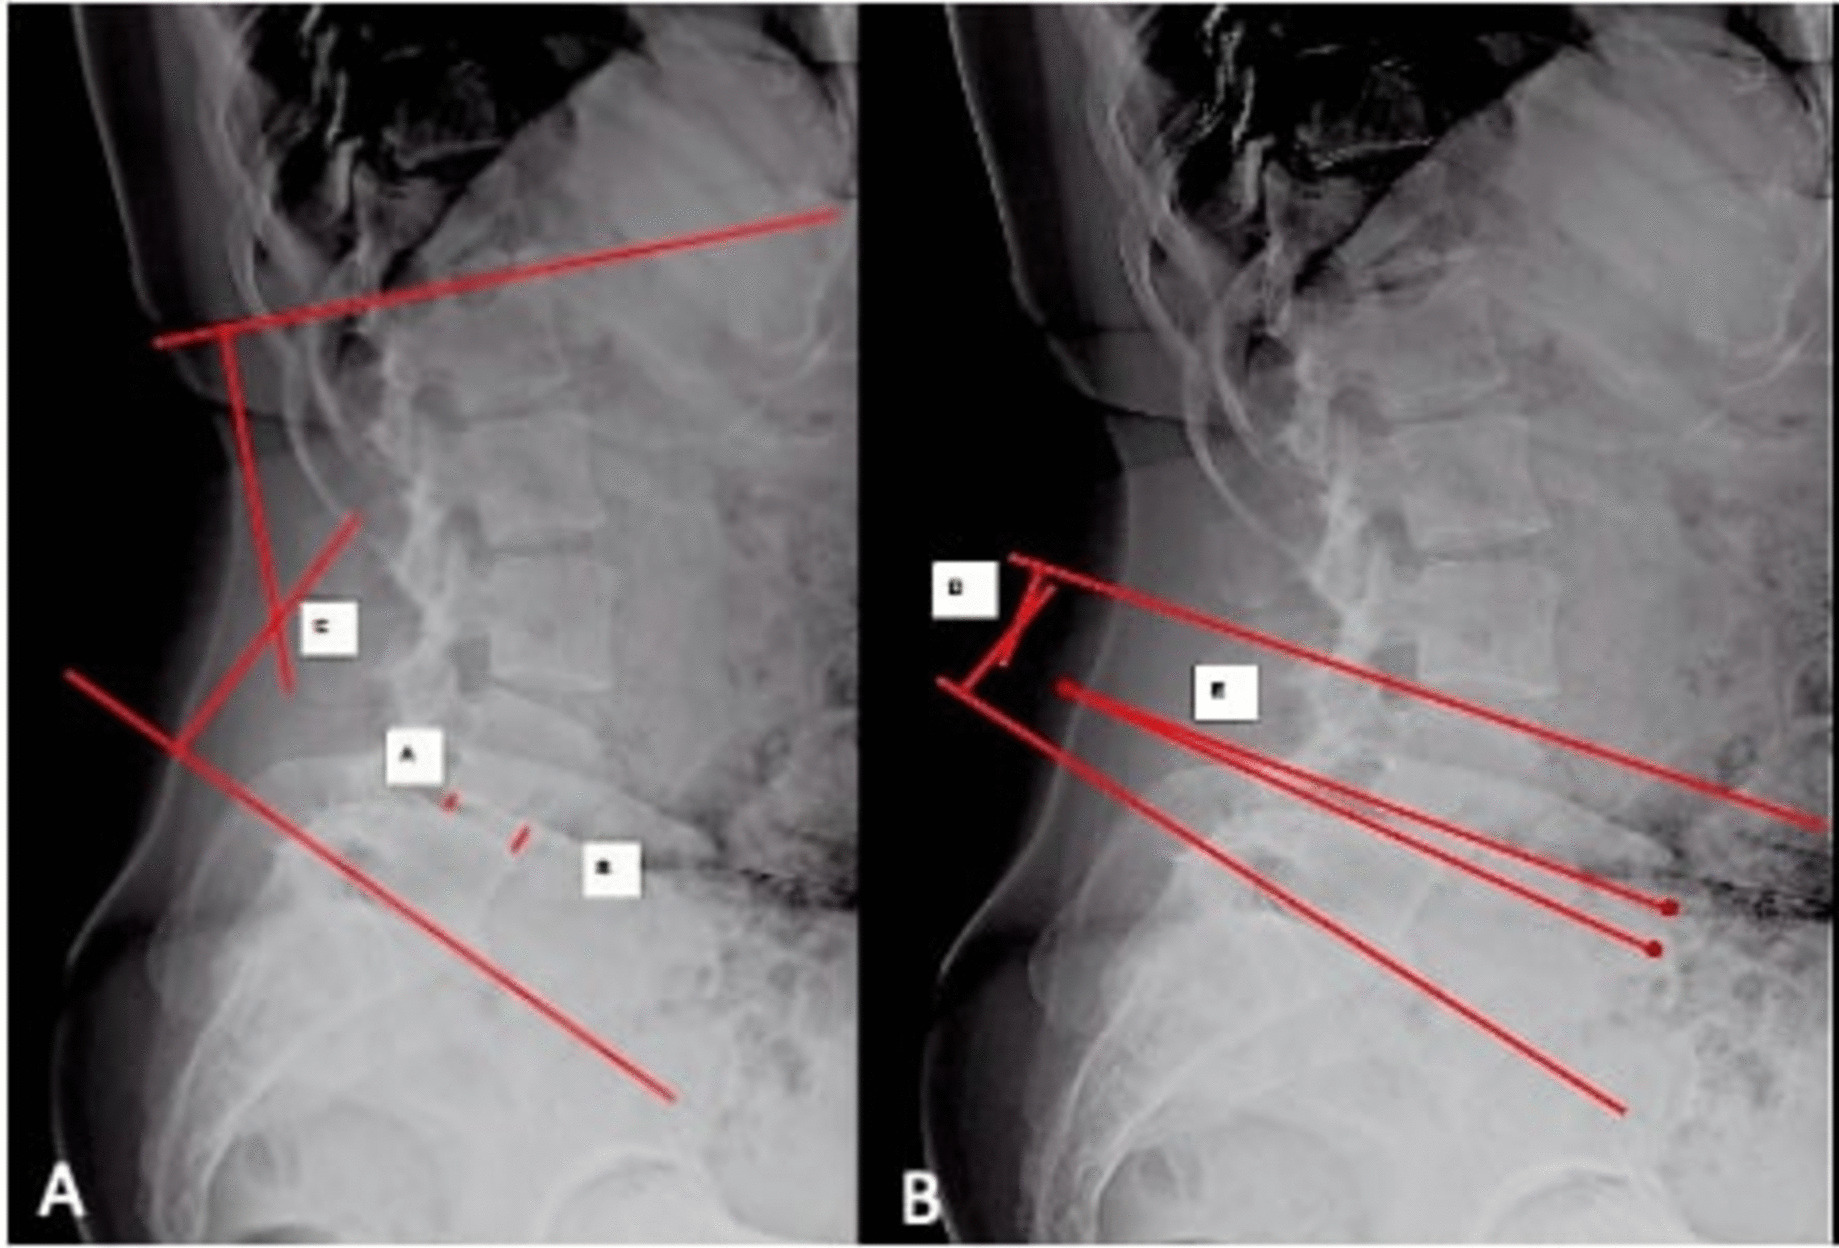

Methods: A single-centre, retrospective study on 74 patients with degenerative and lytic lumbar spondylolisthesis who underwent single level transforaminal lumbar interbody fusion (TLIF) surgery between August 2020 and July 2022 with a minimum follow up of 1 year. Radiographic measures included disc angle(DA), SLL, lumbar lordosis(LL), anterior/posterior disc height(ADH/PDH), spondylolisthesis percentage(SP) and pelvic parameters like pelvic incidence(PI), pelvic tilt(PT) and sacral slope(SS). Surgery-related measures included cage position, spondylolisthesis reduction rate, rod contouring and disc height restoration rate(DHRR). For analysis, change in SLL ≥ 8° indicated increased segmental lumbar lordosis(ISLL), and < 8° indicated unincreased segmental lumbar lordosis(UISLL).